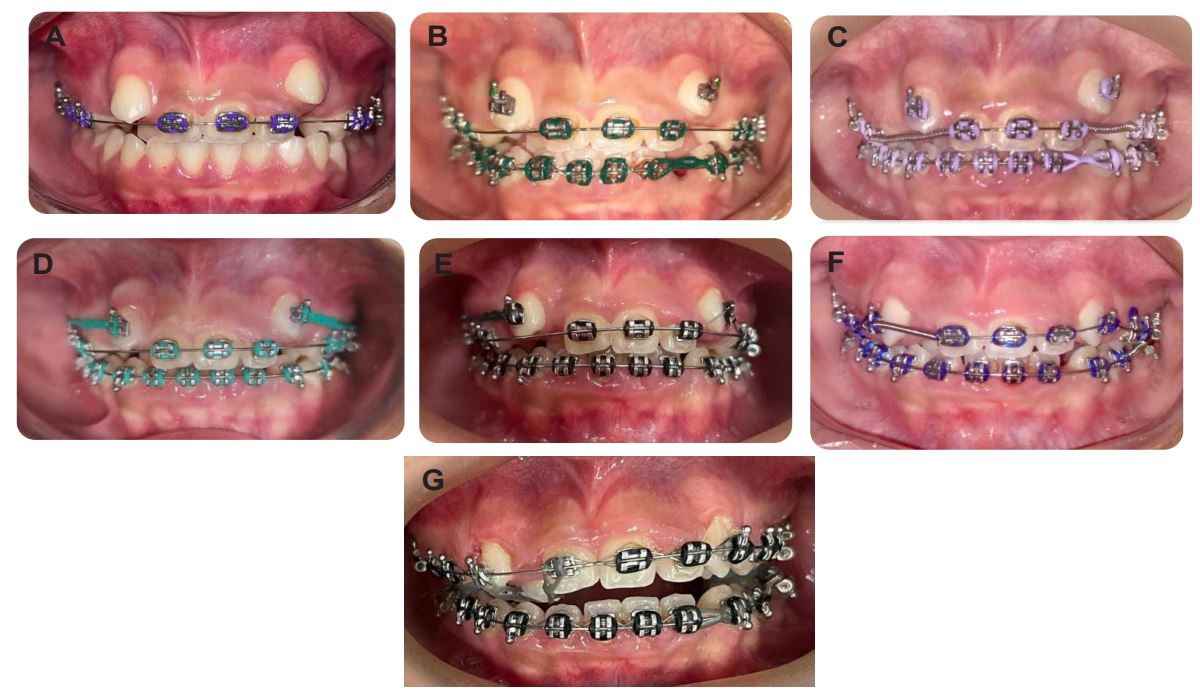

After analysis of the radiographic exams, a fixed mettalic Roth ligh from Morelli with Niti 12 wire was installed, as shown in (Figure 4). Subsequently, the orthodontic appliance was maintained with Niti 12 wire in the upper arch plus cementation of orthodontic bands in elements 16 and 26 (Figure 5), extraction of the two upper primary canines and lower left primary canine that were in prolonged retention and subsequent maintenance (Figure 6) presenting in A the third maintenance and in B was performed installation of the appliance in the lower arch plus maintenance with Niti wire 16 in the upper and lower arches, conjugated ligature from element 32 to 46, Morelli medium elastic chain from tooth 33 to 32 and bonding of teeth 13 and 23, and in C the fifth consultation with evolution of the lower Niti wire 18 with conjugated ligature of element 32 to 44, elastic chain on tooth 33 to 32, steel wire 16 in the upper arch, open spring between teeth 11 and 14 and between 22 and 24 and in D end E the subsequent maintenance until the present moment (Figure 7)

Figure 4: Installation of the metallic Roth appliance (Source: The authors, 2022).

Figure 5: Second orthodontic maintenance; (a) Front view; (b) Left side view; (C) Right Side View. (Source: The authors, 2022).

Figure 6: (a) Extraction of element 73, (b) Extraction of elements 53 and 63. (Source: The Authors, 2023).

Figure 7: (a) Third visit, maintenance of the Niti 14 wire; (b) Fourth consultation, installation of the apparatus in the lower arch; (c) fifth consultation; (d) sixth consultation; (e) seventh maintenance; (f) Eighth maintenance and the last maintenances until the presente moment in G. (Source: The Authors, 2023).